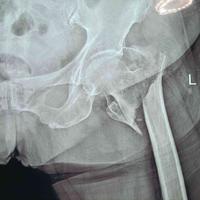

又一例82岁老年转子间骨折,此例移位,嵌

又一例82岁老年转子间骨折,此例移位,嵌插较明显。留存...